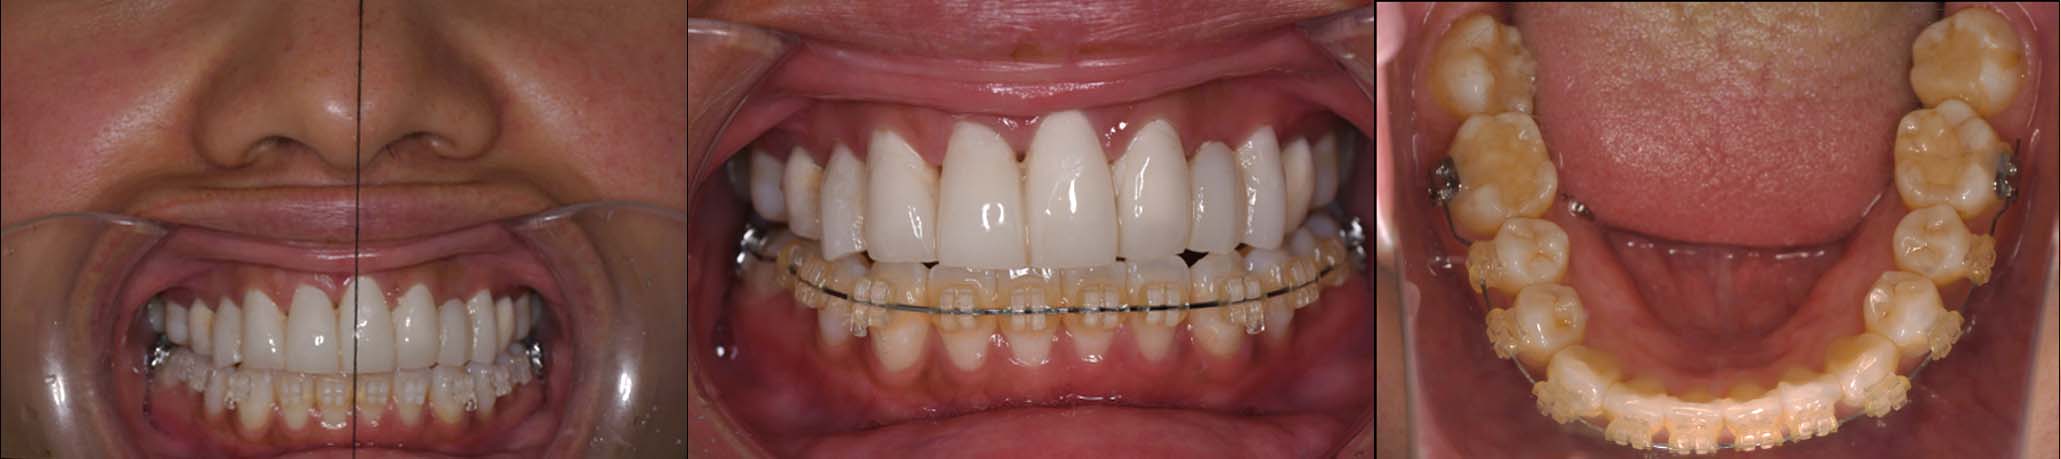

姿勢の変化

2024年 3月 初診時

2024年 10月10日

2025年 12月25日

顔貌の変化